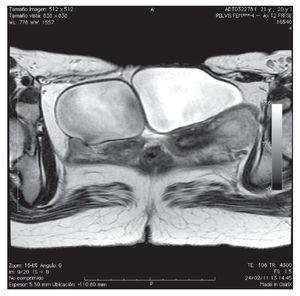

Paciente femenino de 20 años de edad, antecedente de extrofia vesical con cierre espontáneo. A la exploración física, se encuentra la presencia de duplicación de genitales internos y externos (clítoris, vaginas, útero), así como falta de fusión de la pelvis ósea (Figura 1). Paciente acudió al servicio de urología, por la presencia de dolor en el flanco derecho y una masa palpable. Se le realizó tomografía, donde se evidenció una bolsa hidronefrótica derecha y la presencia de dos vejigas con uretras independientes y un útero doble (Figuras 2 y 3). En la resonancia magnética, se pudieron identificar dos vejigas no comunicantes con interface entre las dos (Figuras 4 y 5). Se envió a genética reportándose cariotipo de 46XX. Se realizó cistografía, donde se evidenció la presencia de duplicación vesical completa y presencia de reflujo vesicoureteral derecho grado IV. Se realizó cistoscopia con lente pediátrico de 30 grados, observando en la uretra derecha hemivejiga con meato ureteral ortotópico dilatado, sin visualizarse el izquierdo, ni conexión a hemivejiga izquierda. Se realizó el mismo procedimiento en la uretra izquierda, visualizando uréter ortotópico y eyaculante. Se diagnosticó doble sistema genitourinario completo, con reflujo vesicoureteral grado IV y exclusión renal derecha. Se programó para nefroureterocistectomía derecha.

Figura 4. En la resonancia magnética se pudieron identificar dos vejigas no comunicantes con interface entre ellas.

Figura 5. Otra proyección de la resonancia magnética. Se identifican dos vejigas no comunicantes con interface entre ambas.